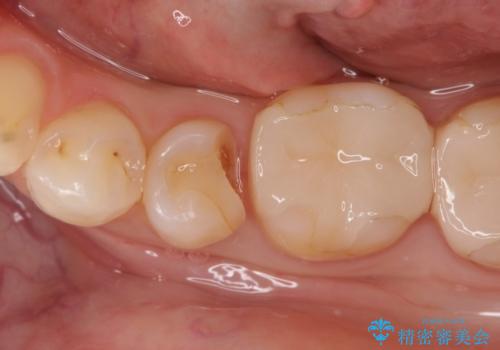

虫歯の治療(セラミックインレー)

- 定期検診にて虫歯が見つかり、セラミックインレーに治療を行っております。

e-max プレスインレーにて修復治療を行っているため適合性及び審美性の高い治療を行うことができます